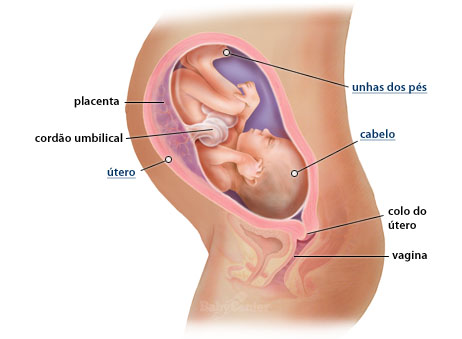

“Mamãe no 7º mês: Pode apresentar dores nas costas, falta de ar, sensibilidade e/ou secura nos olhos, alergias, e problemas gastrointestinais em virtude da compressão do útero sobre o intestino e o afrouxamento da musculatura desta estrutura. Ela também pode ter câimbras, provocadas geralmente pela carência de ferro. Além disso, nessa fase ela tende a se apresentar mais inchada, e com os seios significantemente maiores (liberando colostro); e as estrias tendem a surgir – podendo ser prevenidas hidratando bem o corpo e a pele.Corrimentos vaginais são comuns, assim como incontinência urinária. Isso aumenta as chances de infecções, que têm prurido e aumento do número de micções como sintomas clássicos.

“Nesse período o bebê passa a maior parte do tempo acordado. Nessa fase, seu corpo cresce mais que a cabeça, tornando corpo e membros proporcionais. O bebê inicia essa fase com aproximadamente 700 gramas, encerrando com 1250 gramas, e cerca de 30 centímetros.

Ele se apresenta rosado, em virtude da formação dos capilares sanguíneos; com a pele bem fina, e começa a engordar. As mãos já estão bem formadas, e podem abrir e fechar. Como o cérebro e as terminações nervosas estão relativamente desenvolvidos, assim como o sistema imunológico, ele também já é capaz de ter sensações táteis, ouvir e perceber a luz. Falando nisso, seus olhos já estão completamente desenvolvidos e, nesse mês, já poderão ser abertos e fechados.

Como as narinas já se apresentam abertas, e os pulmões se desenvolvem significantemente; o bebê é capaz de respirar pelo nariz, caso nasça prematuramente. No caso dos meninos, é nesse período em que os testículos costumam descer.” (https://www.brasilescola.com)